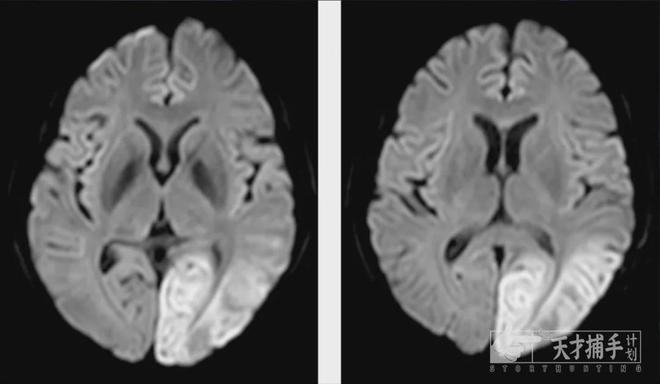

±ØÍþ´Ó¡°È«ÇòÊ׿¿´Ë¼Â·µÏÕï¶ÏµÄ³õÐÄʹÃüÖÂÁ¦³ÉΪ¡°Öǻݡ±¾«×¼Õï¶ÏÏÈÐÐÕß(ͼ1)